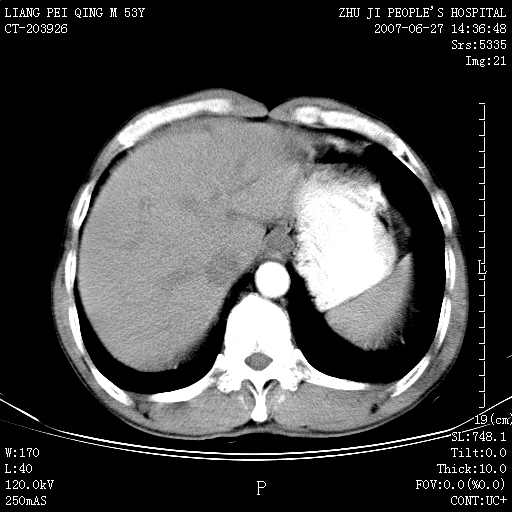

以下是引用余辉在2007-6-27 18:46:00的发言:[br]病灶多发,内可见大片状低密度区,病灶病灶等密度区轻度强化,动脉期后期病灶低密度区与高密度区对度增加,考虑1淋巴瘤2转移瘤3血管内皮细胞瘤(不知有否静脉期及延迟期扫描)

以下是引用zzzzhhhhaaaannnn在2007-6-27 20:44:00的发言:[br]脾脏 肋骨转移可能性大,下腔静脉内有癌栓

以下是引用狙击手在2007-6-28 10:35:00的发言:[br]1:定位:来源于脾脏。2:强化:强化,但不均匀。3:下腔静脉癌栓?下腔静脉充填不均匀与增强时间有关,延时即可明确。4:肋骨破坏?看起来并不确切。综上考虑几个最常见诊断:1;淋巴管瘤;2;血管内皮肉瘤(高度恶性,早期即可转移,常见肝,肺,骨)3;转移瘤(无特征性,只有肝或其它腹腔脏器有类似病变时,才可提示之)